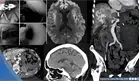

Hemorragia gastrointestinal provocó edema cerebral en paciente con Telangiectasia y malformación hepática